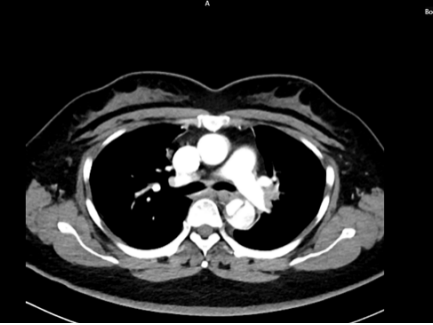

71岁男性,突发剧烈胸痛,既往有长期高血压、糖尿病病史。

时间就是生命。医生会结合症状,快速进行以下检查:医院会根据CT血管成像(CTA)进行诊断。如确诊为主动脉夹层,则会进行紧急处理,立即镇痛、控制血压和心率(如静脉注射β受体阻滞剂)。

A型夹层:开放手术

手术是“巨创手术”,需要在深低温停循环下,用人工血管替换掉被撕裂的主动脉段,就像换掉一段坏掉的水管。手术风险高,但这是唯一能救命的方法。